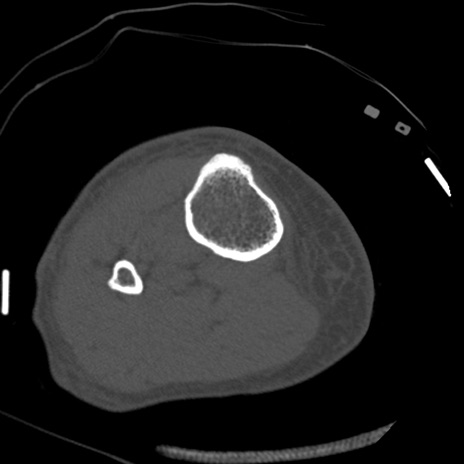

症例28 右膝関節CT(横断像)

右膝関節CT